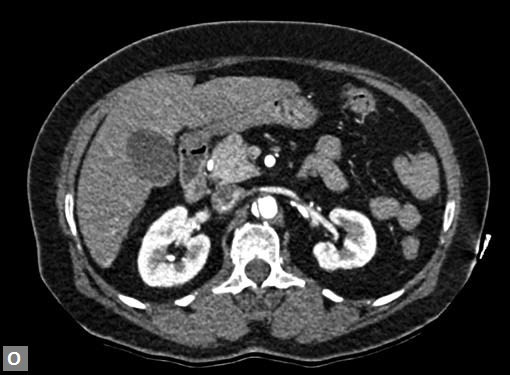

Any part of aorta can get affected by aneurysms. Focal

dilations can be saccular or fusiform. Atherosclerosis is

the most common cause. Tubercular and other infective

aneurysms, traumatic ones are also uncommonly seen. Size

of the aneurysm, proximity to origin of main vessels, relation

with branching and bifurcation, presence of mural thrombus

are the critical information sought on CT.

Contained leak, rupture are the feared complications.

Aortoenteric fistula is a rare but potentially catastrophic

complication. Aneurysmal dilation is common in ascending

aorta (Figs 19W to Y).

CT is also useful in surveillance of diagnosed aneurysms.